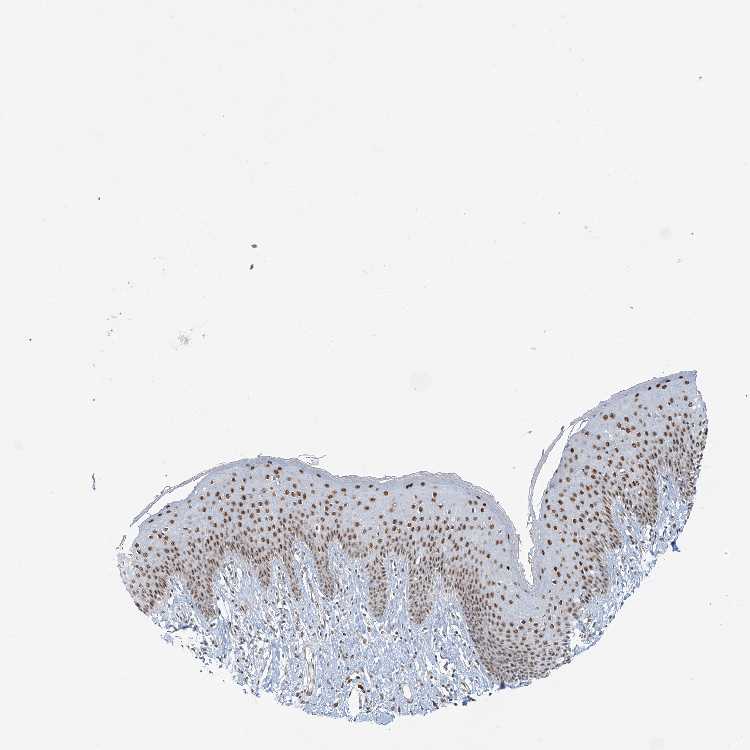

TISSUE PRIMARY DATA SKIN 1 Show tissue menu

SKIN 1 - Antibody stainingi

Antibody staining in the annotated cell types in the current human tissue is reported as not detected, low, medium, or high, based on conventional immunohistochemistry profiling in selected tissues. This score is based on the combination of the staining intensity and fraction of stained cells.

Each image is clickable and will lead to virtual microscopy that enables deeper exploration of all samples and also displays staining intensity scores, fraction scores and subcellular localization as well as patient and tissue information for each sample.

Antibody HPA030902Antibody HPA030903

Langerhans HighHigh

Fibroblasts HighHigh

Keratinocytes HighHigh

Melanocytes HighHigh